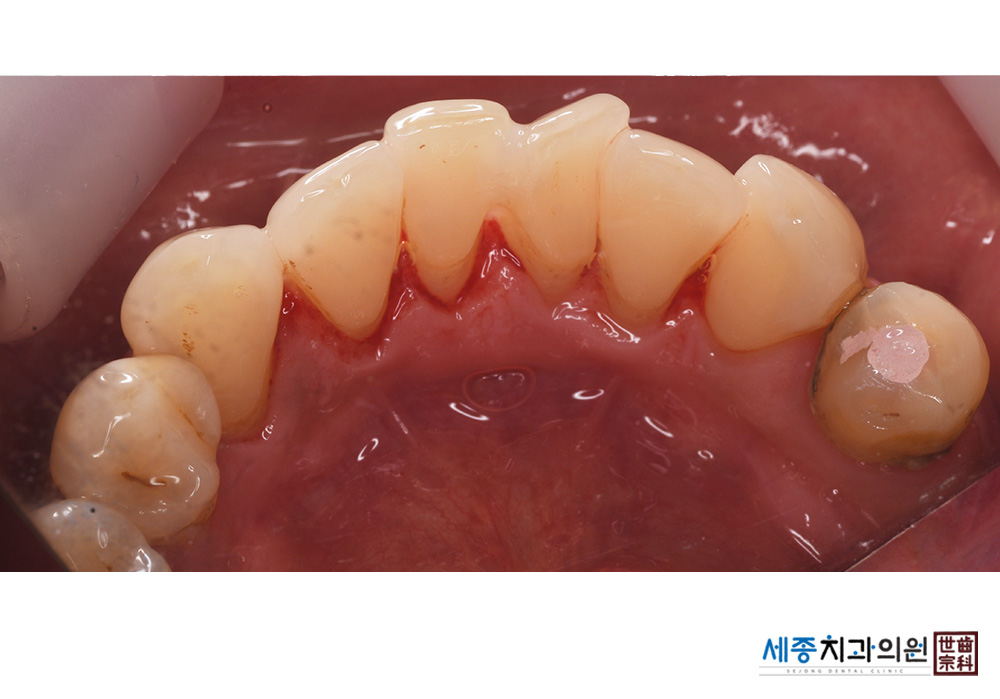

[스케일링] 치주질환 예방 스케일링

치료전 : 2021-01-27

치료후 : 2021-01-27

가글마취&저주파 스켈러를 사용한 스케일링